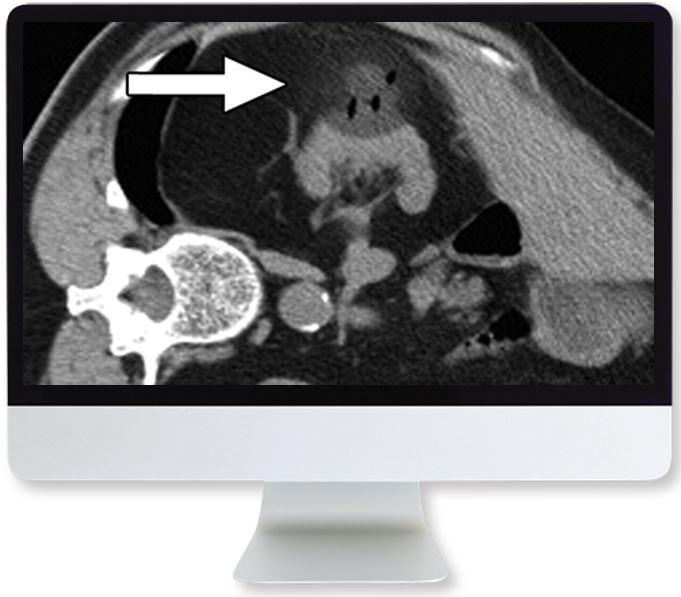

This course provides comprehensive instruction on the appropriate indications and protocols for cross-sectional renal imaging and helps participants accurately diagnose the full spectrum of renal abnormalities in children and adults.

- Imaging of Solid Renal Masses—V. Sai

- Cystic Renal Masses—N. Curci

- Vascular Diseases of the Kidneys—M. Kolber

- Renal Infection and Inflammation—M. Sakala